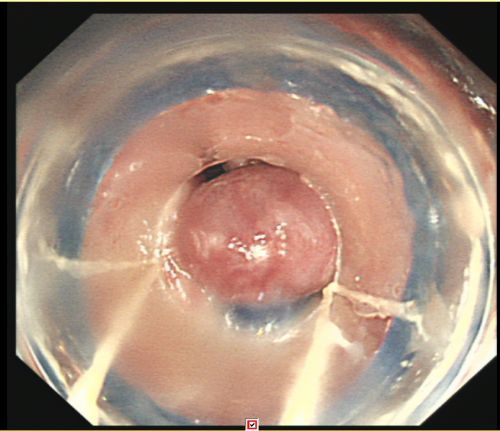

胃镜下可以看到食管静脉重度曲张。

经过积极抢救,易某病情稍稳定,被转入综合内科病房继续治疗。入院进一步完善胃镜检查结果提示:食管静脉重度曲张,加上血管壁极薄,随时可能破裂大出血。